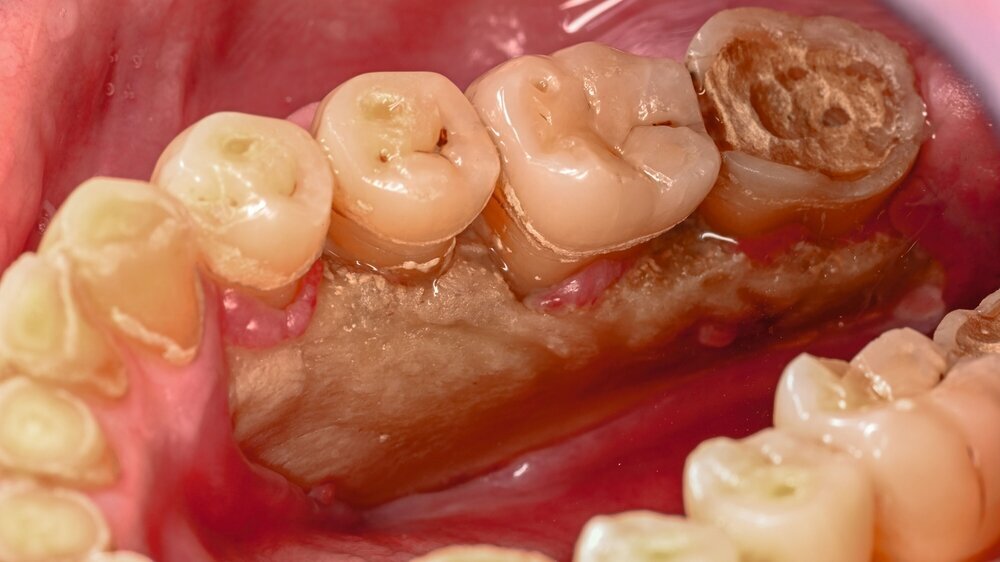

Der Patient stellte sich mit freiliegendem Knochen in Regio 43 bis 47 und mehreren gelockerten Zähnen vor. 45 und 46 waren devital. Als klinische Besonderheit fiel auf, dass sich innerhalb der Nekrosezone kleinflächige Weichgewebsareale darstellten, die in dieser Form bei klassischen Osteonekrosen üblicherweise nicht beobachtet werden. Eine klassische Vincent-Symptomatik bestand nicht. Drei Wochen zuvor war eine Herpes-Zoster-Infektion dermatologisch diagnostiziert und zunächst stationär behandelt worden. Der Patient erhielt eine intravenöse, antivirale Therapie, die bei Entlassung oralisiert wurde.

Zum Zeitpunkt der Erstvorstellung in der kieferchirurgischen Ambulanz zeigten sich keine klassischen Herpes-Zoster-Effloreszenzen im Gesicht. Eine antiresorptive Therapie oder Bestrahlung lag nicht vor, sodass eine Herpes-Zoster-assoziierte Osteonekrose im Sinne einer Ausschlussdiagnose festgestellt wurde. Anamnestisch bestand ein gut eingestellter Diabetes mellitus Typ 2 als potenziell immunkompromittierende Grunderkrankung. Die Knochenszintigrafie zeigte eine deutliche Stoffwechselsteigerung im betroffenen Bereich, vereinbar mit einer infizierten Osteonekrose.